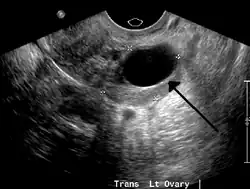

A simple ovarian cyst of most likely follicular origin

A 2 cm left ovarian cyst as seen on ultrasound

Ovarian cysts are usually diagnosed by pelvic ultrasound, CT scan, or MRI, and correlated with clinical presentation and endocrinologic tests as appropriate.[15] Ultrasound is the most important imaging modality, as abnormalities seen in a CT scan sometimes prove to be normal in ultrasound.[5][8] If a different modality is needed, then MRIs are more reliable than CT scans.[5]